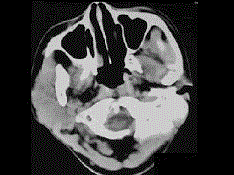

问题 19岁,女性患者,右侧面颊部肿胀一年,CT检查如图所示,请选择最佳答案 ( )

选项 A、右颊部横纹肌肉瘤 B、右颊部血肿 C、右颊部血管瘤 D、右颊部脂肪瘤 E、右颊部神经纤维瘤

答案 C